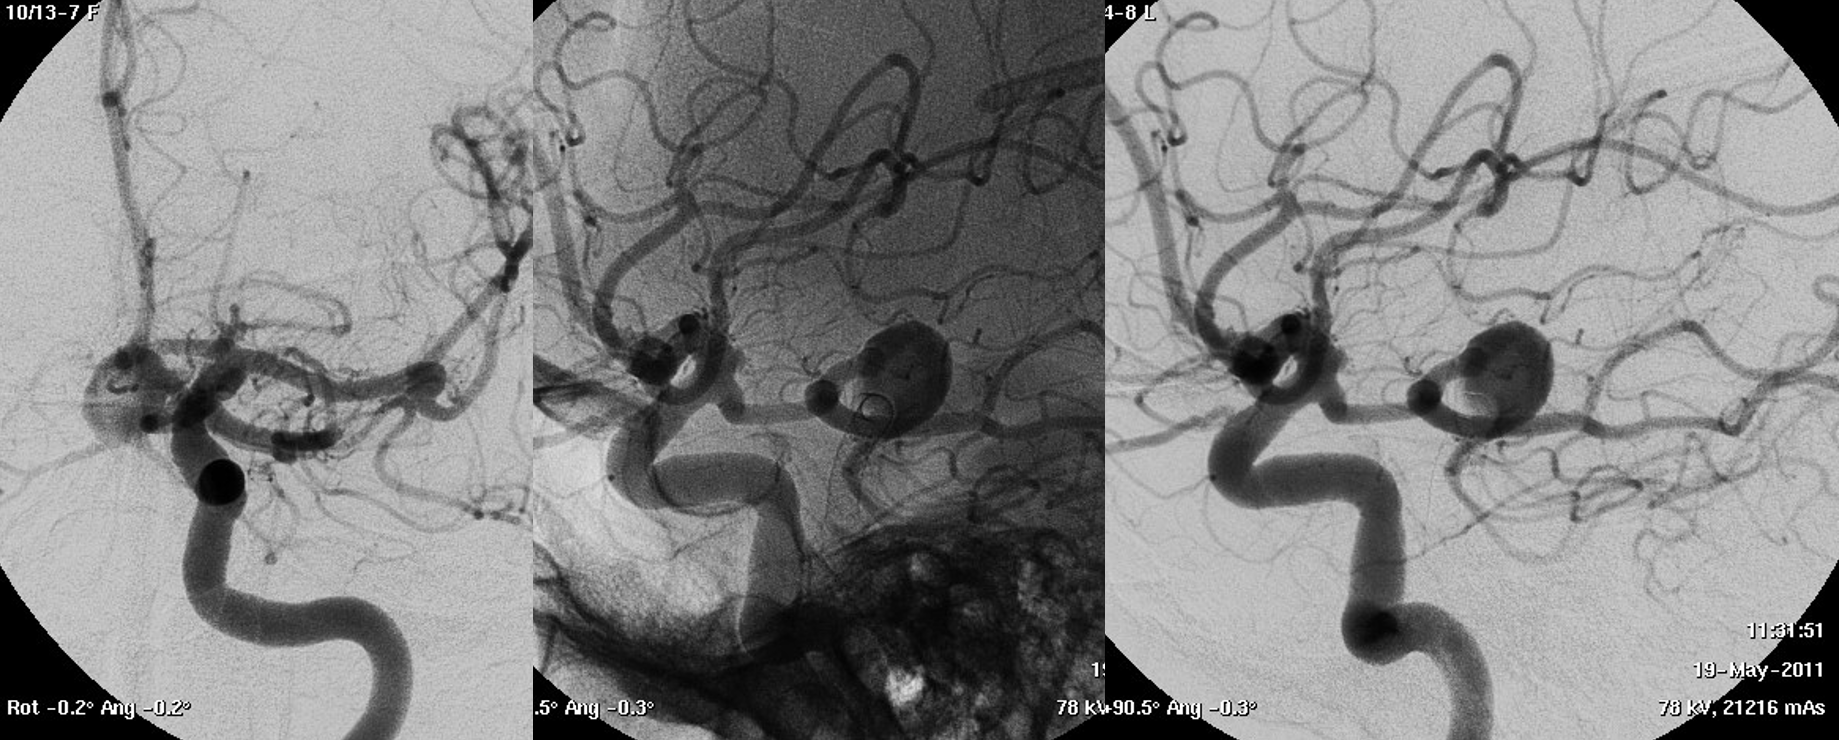

A symptomatic unruptured MCA bifurcation aneurysm in a young woman

This video was made with Horos from the original 3D dataset (3D 5 seconds 15 cm FOV acquisition, manually injecting pure contrast – 250 mg/ml – with a 20 ml syringe).